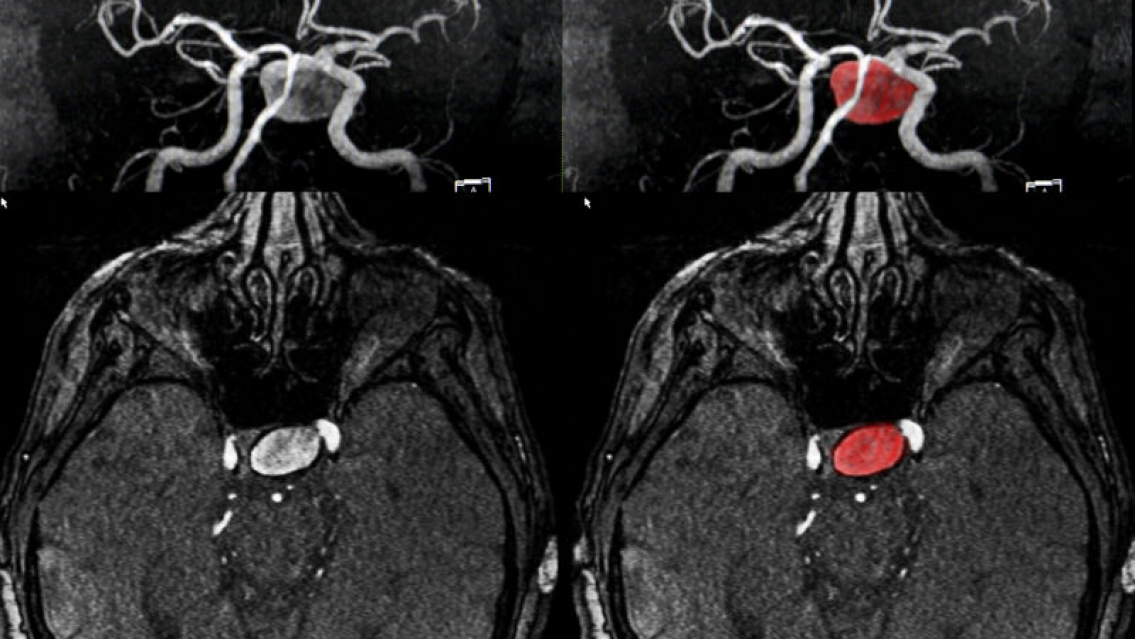

A los 18 años, Ella Pick experimentó lo que creyó ser un malestar producto de la resaca durante unas vacaciones con amigas. Sin embargo, al regresar a casa y retomar su rutina, sus síntomas se intensificaron. Migrañas persistentes y el hundimiento de su ojo izquierdo la llevaron a buscar ayuda médica, donde recibió la devastadora noticia de que tenía un tumor cerebral incurable e inoperable. Le dieron un pronóstico de vida de solo 12 meses.

Desde entonces, la vida de Ella quedó en pausa mientras asimilaba su diagnóstico y se preparaba para lo inevitable. A pesar del golpe devastador, Ella decidió mantener una actitud positiva y continuar con su vida lo mejor que pudo. Se sometió a un tratamiento de radioterapia en un esfuerzo por detener la progresión del tumor, y aunque en su última revisión se informó que el tumor estaba estable, ella sigue abierta a cualquier opción que pueda prolongar su tiempo.